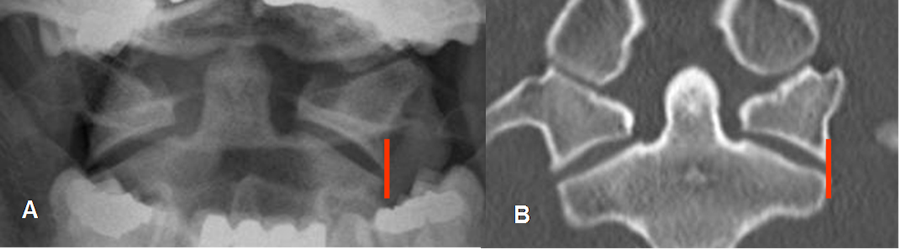

Fig 190. Odontoides normal.

A: Rx AP y B: TAC reconstrucción coronal. Odontoides normal, con alineación de las masas laterales de C1 y C2.